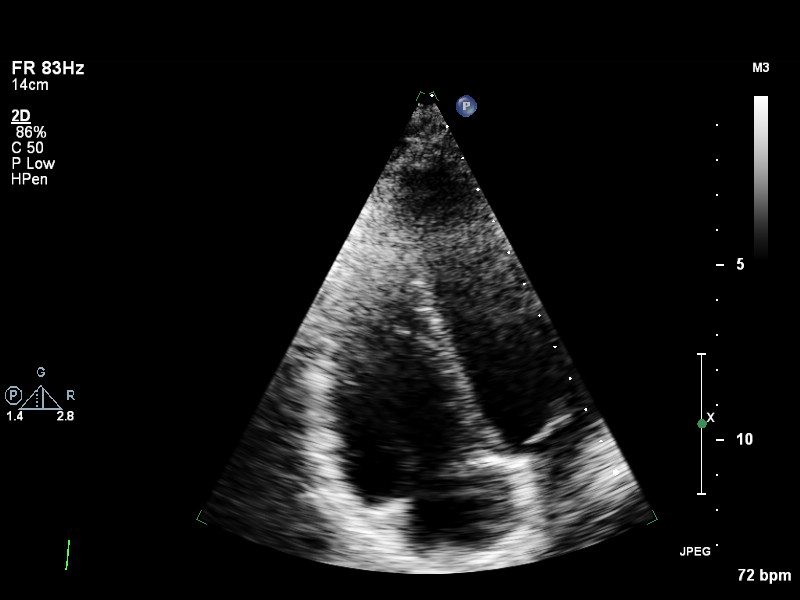

ImageView NameDescription

plax-full-la plax-full-la Parasternal long-axis, sector covers whole LA; intended for LA measurements

plax-full-lv plax-full-lv PLAX with imaging sector covering LV but not the whole LA

plax-full-mv plax-full-mv PLAX centered on MV (heavy zoom losing LA/LV parts or MV colour)

plax-full-out plax-full-out Zoomed-out PLAX

plax-full-rv-ao plax-full-rv-ao Focus on RV & aorta or colour Doppler over RV/AV/Aorta

plax-tv plax-tv Parasternal inflow view including tricuspid valve

plax-valves-av plax-valves-av PLAX focused on the aortic valve

plax-valves-mv plax-valves-mv PLAX focused on the mitral valve